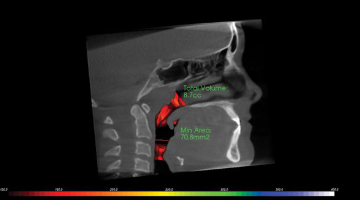

This is a sagittal cross section with a completed airway analysis of the nasopharyngeal and oropharyngeal airway.

The many features of the software programs include the ability to take screenshots of TMD issues, view the sinus, and analyze a patient’s airway volume. They also eliminate the need for a separate cephalometric image in orthodontic cases. Lastly, the software can generate a panoramic radiograph quickly and easily, albeit with a bit of practice.